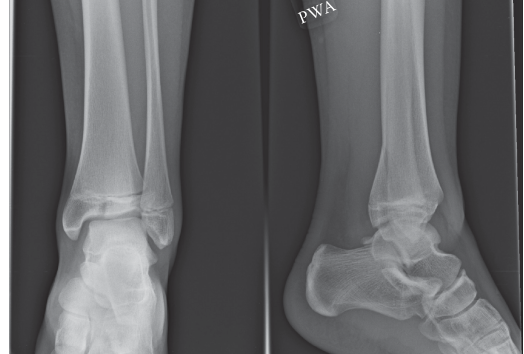

- Plain Radiographs: Initial assessment typically involves AP, lateral, and oblique views of the ankle. These provide a basic understanding of fracture displacement and configuration, often suggesting the diagnosis.